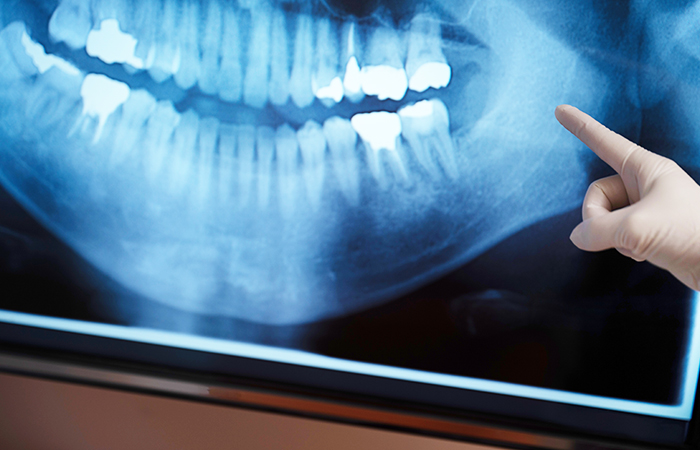

検査・診断

まずは、痛みがある歯やその周囲のレントゲン写真を撮影し、歯の根っこの状態や感染の進行度を確認します。

歯科用CTによる

的確な診査・診断

根管治療では、根管の状態を的確に把握することがとても大切です。当院では、3Dで撮影でき、歯や顎の骨、神経や血管の位置などを映し出す「歯科用CT」を使って、通常のレントゲンでは見えにくい根管の形や感染の広がりなどを確認しています。これにより見落としを防ぎ、より精密で的確な治療が実現します。